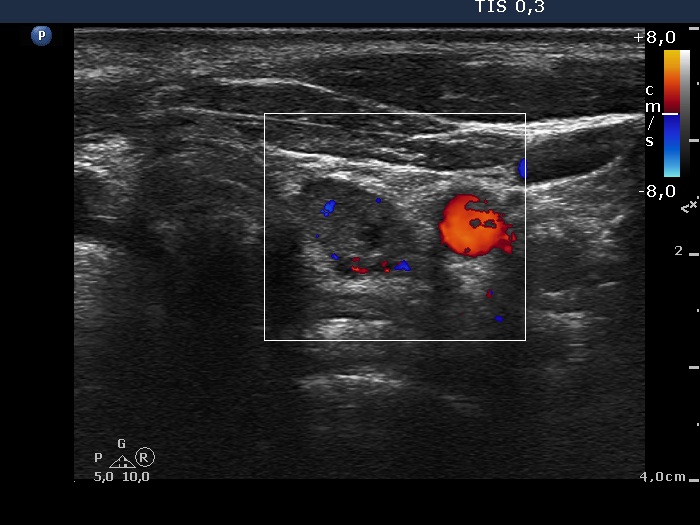

Ultrasonography: The thyroid was echonormal. There were several hypoechogenic nodules presenting microcalcifications in both lobes and in the isthmus. There was a similar lesion under the lower pole of the left lobe. The vascularization of the lesions was variable.

Ultrasonography. There was no parenchyma according to the right thyroid bed. There were two hypoechogenic lesions in the lower pole of the left thyroid bed. Both were irregular in shape and presented cystic degeneration and microcalcifications. There was a reactive-type lymph node ventral to the previously described lesions.